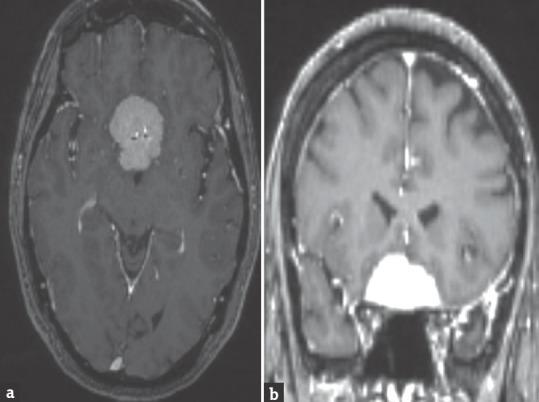

Postoperative visual loss is a dreaded complication following transcranial excision of tuberculum sella meningioma. Visual deterioration is commonly noticed immediately after surgery, and delayed deterioration after 72 h is uncommon. We report a case of delayed postoperative deterioration in a 48-year-old female and discuss the possible mechanisms.

术后视力丧失是经颅切除鞍结节脑膜瘤后一种可怕的并发症。视力恶化通常在手术后立即被注意到,72小时后出现延迟恶化的情况并不常见。我们报告一例48岁女性术后延迟恶化的病例,并讨论其可能的机制。